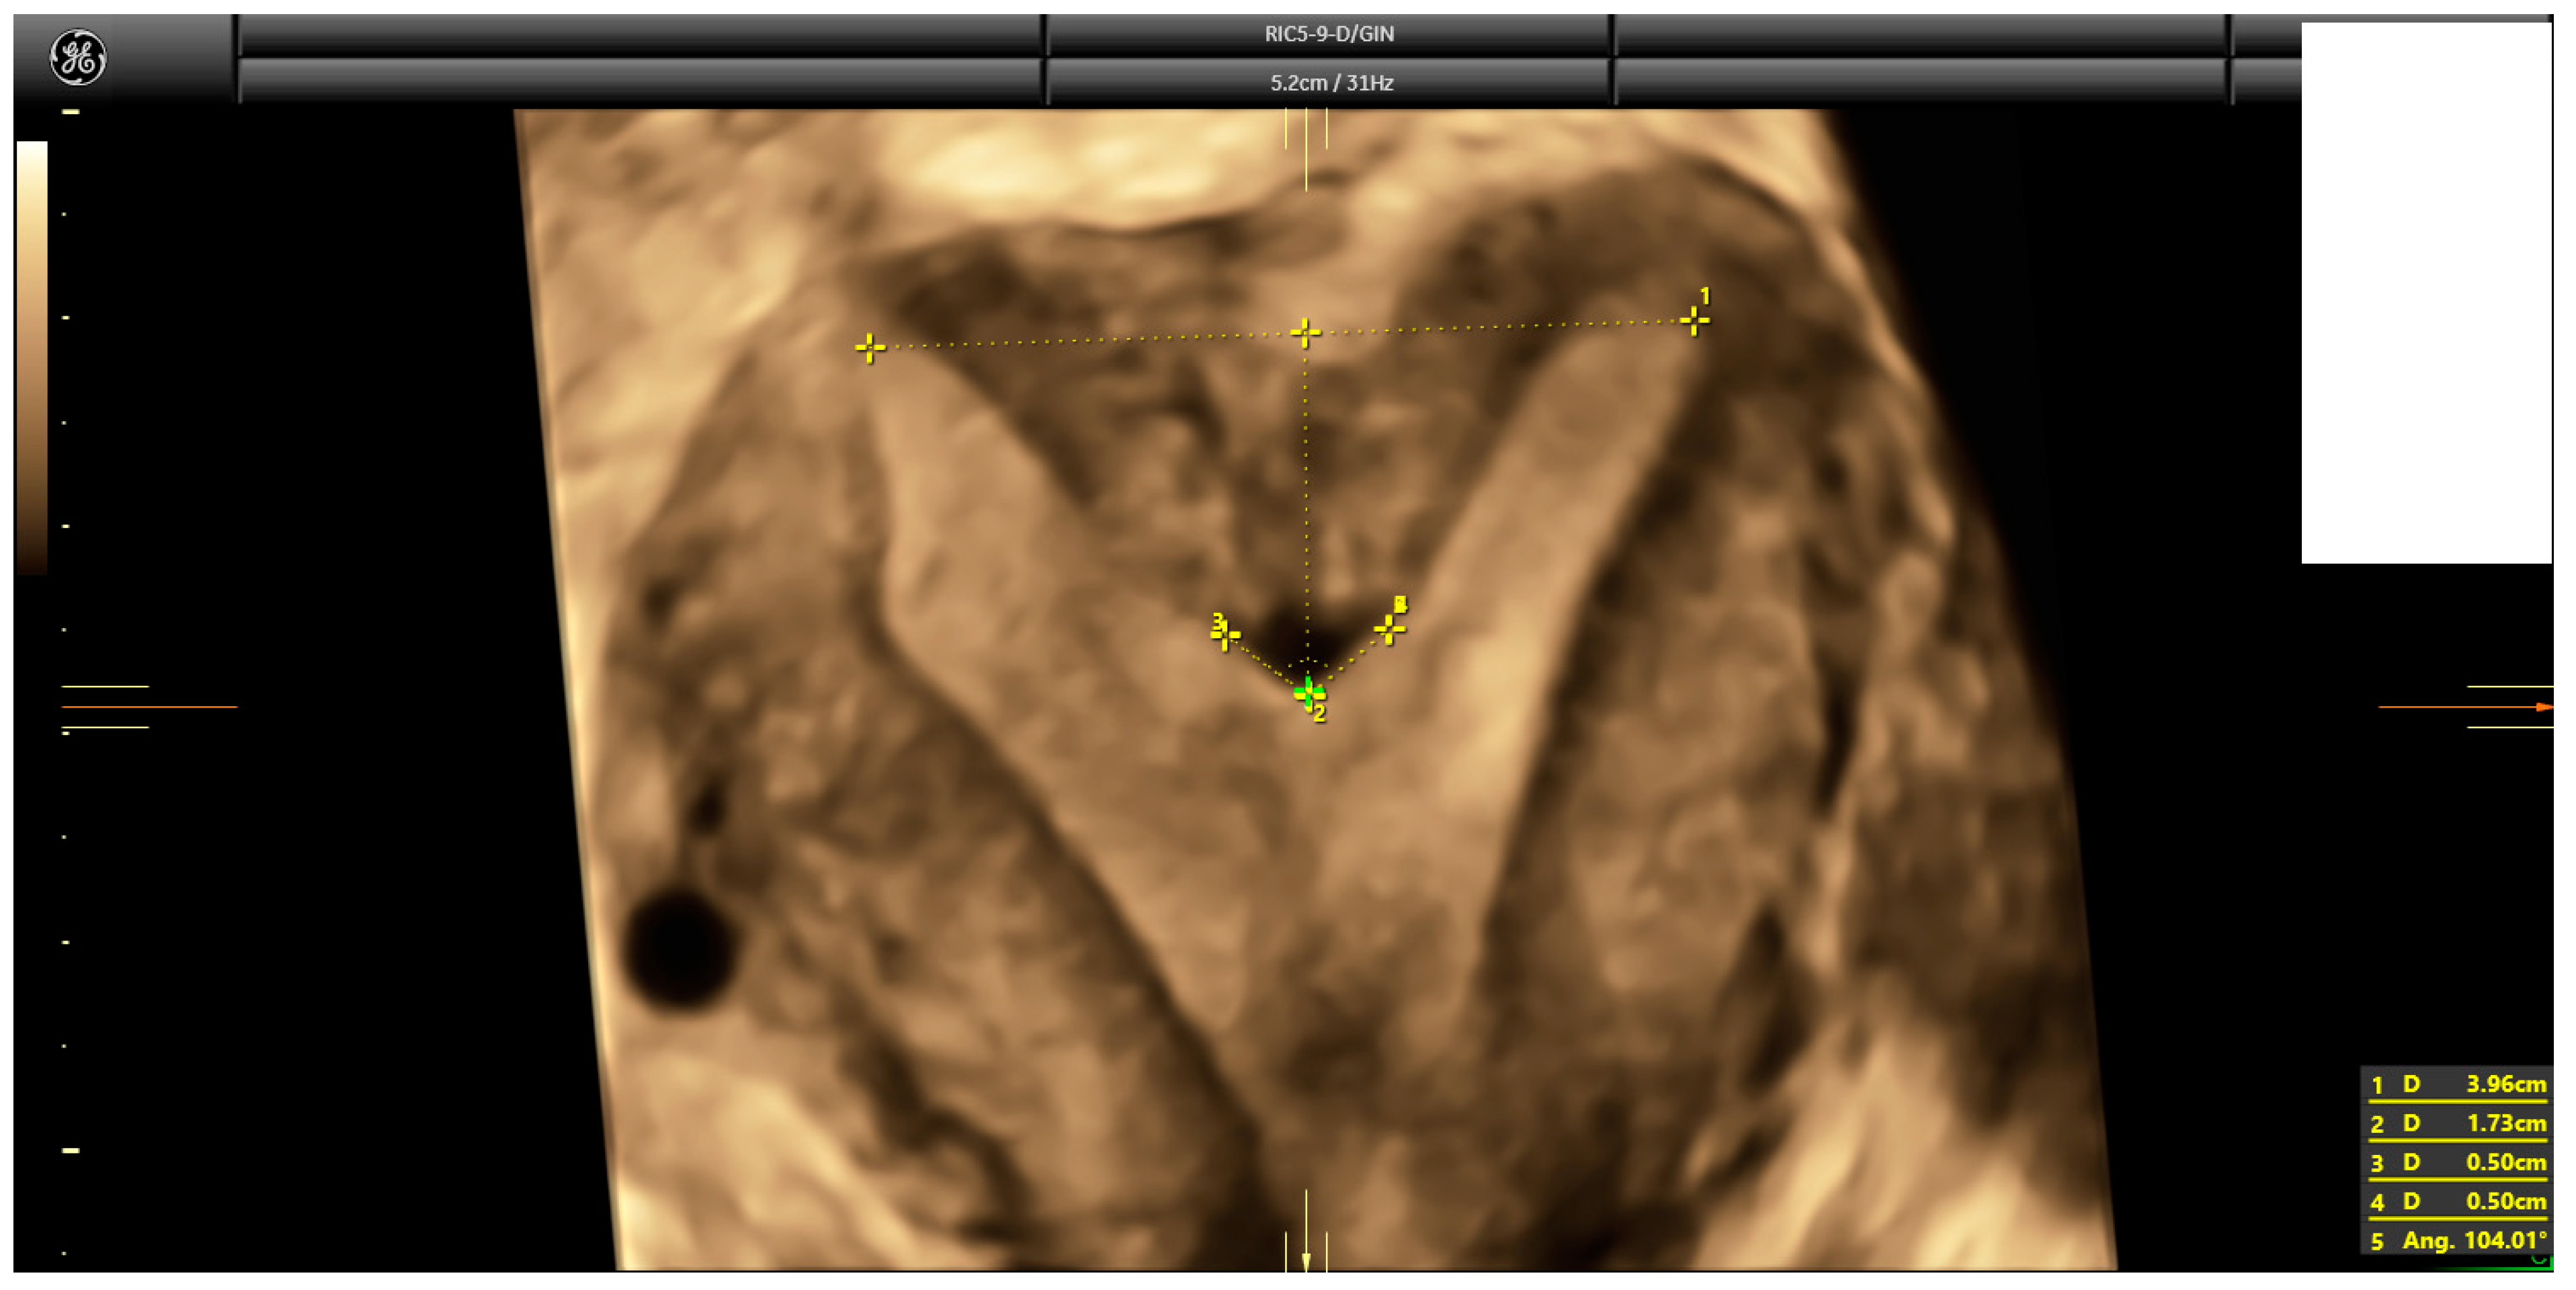

2.3. Ultrasound Evaluation

- Ludwin, A.; Martins, W.P. Correct measurements of uterine fundal internal indentation depth and angle: An important but overlooked issue for precise diagnosis of uterine anomalies. Ultrasound Obstet. Gynecol. 2021, 58, 497–499. [Google Scholar] [CrossRef] [PubMed]

| Indentation length * | 2.0 mm (2.3) | Range: 0–37 mm |

| Uterine Wall thickness * | 10.0 mm (3.7) | Range: 3.3–26.0 mm |

| Indentation angle * | 169° (21.0) | Range: 0–180° |

| I:WT ratio * | 20% (27.0) | Range: 1–596% |